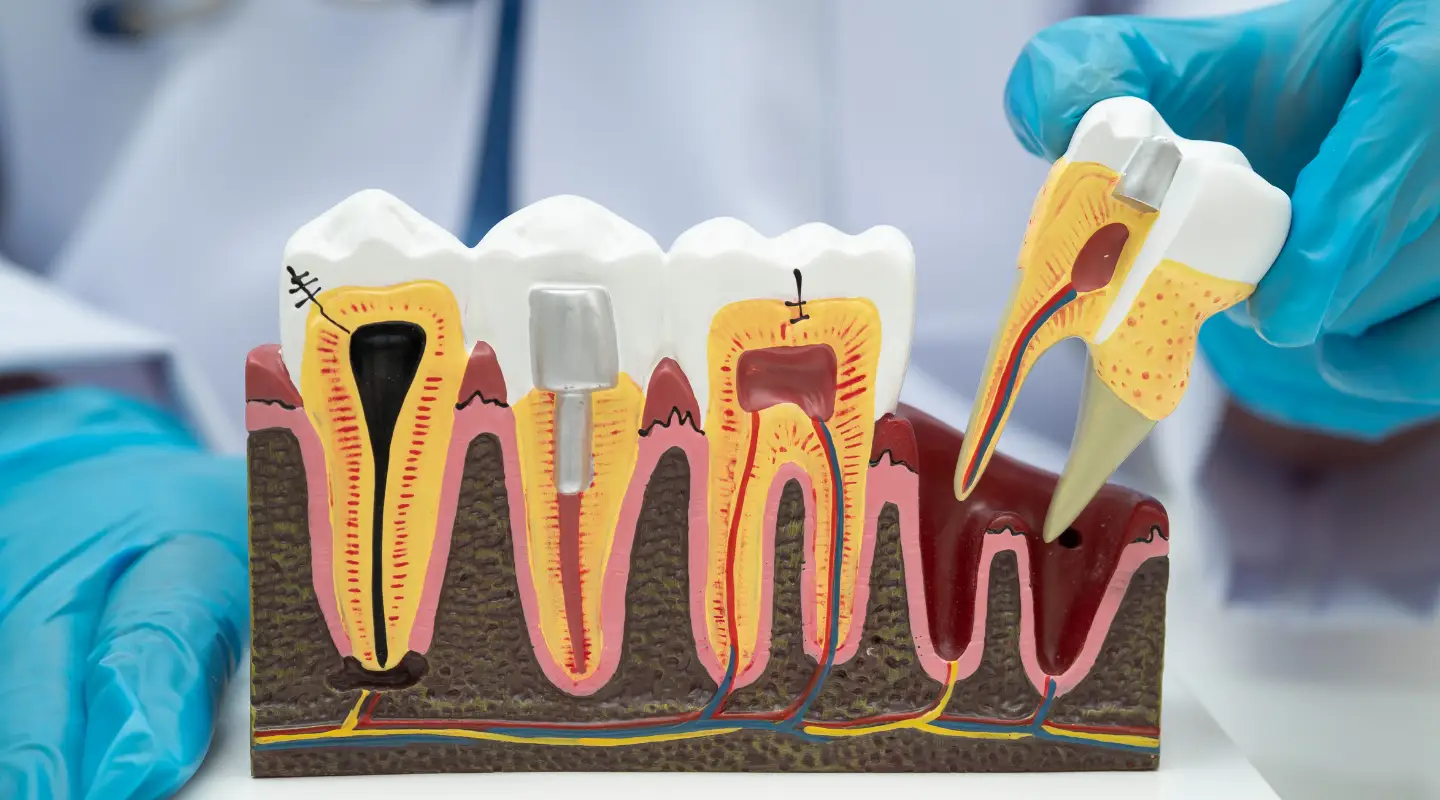

Your Implant Journey — Step by Step

Dr Noor has advanced training in implant dentistry and has placed over 500 dental implants during his career. He provides solutions including single implants and full jaw restorations, helping patients restore missing teeth with natural-looking, long-lasting results.